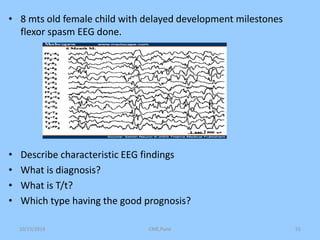

1. The document discusses EEG patterns and findings in various neurological conditions seen in children. It includes descriptions of normal EEG findings as well as abnormal patterns seen in conditions like absence seizures, West syndrome, benign childhood epilepsy with centrotemporal spikes, Lennox-Gastaut syndrome, non-convulsive status epilepticus, subacute sclerosing panencephalitis, and herpes encephalitis.

2. Case studies are presented with clinical histories and EEG findings to illustrate different pathologies. Treatment options are also mentioned for many of the conditions.